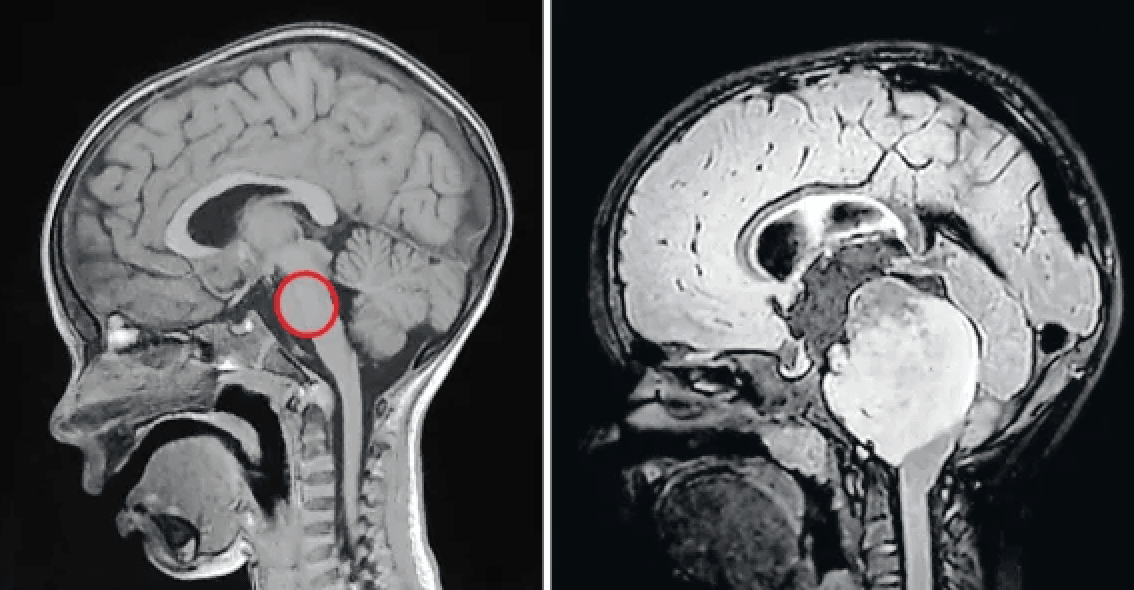

Podczas serii skanów MRI obserwowałem, jak guz całkowicie znika. Nie znam drugiego takiego przypadku na świecie, Lucas jest wyjątkowy.

Siedmioro innych dzieci objętych badaniem przeżyło kilka lat od postawienia diagnozy (co jest dużym sukcesem), u Lucasa guz całkowicie zniknął. Medycyna nie zna drugiego takiego przypadku na świecie, ale lekarze nie mają wątpliwości – 13-letni obecnie chłopiec jest wolny od DIPG. Pojawia się kluczowe pytanie: co takiego wydarzyło się w jego organizmie, że wyzdrowiał?